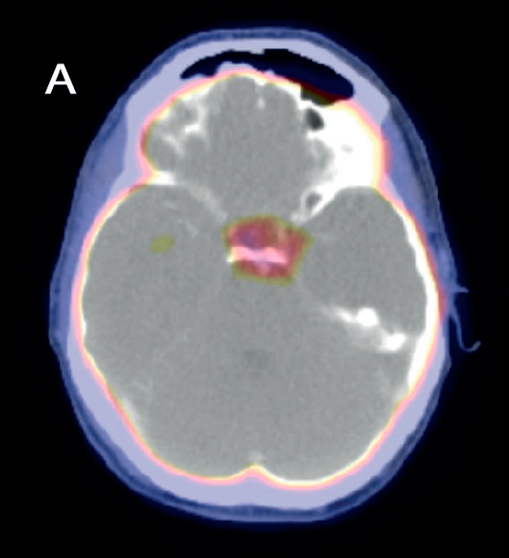

Se realiza diagnóstico de deficiencia de arginina-vasopresina central y se inicia desmopresina intranasal a demanda. Se realiza una RMN con enfoque selar, que reporta una lesión hipofisaria que compromete glándula y tallo hipofisario (Figura 1).

En la evolución se realiza RNM de control 2 años posteriores a primera RMN, que evidencia disminución del tamaño de la lesión tanto en el tallo hipofisario como de la hipófisis (Figura 2).